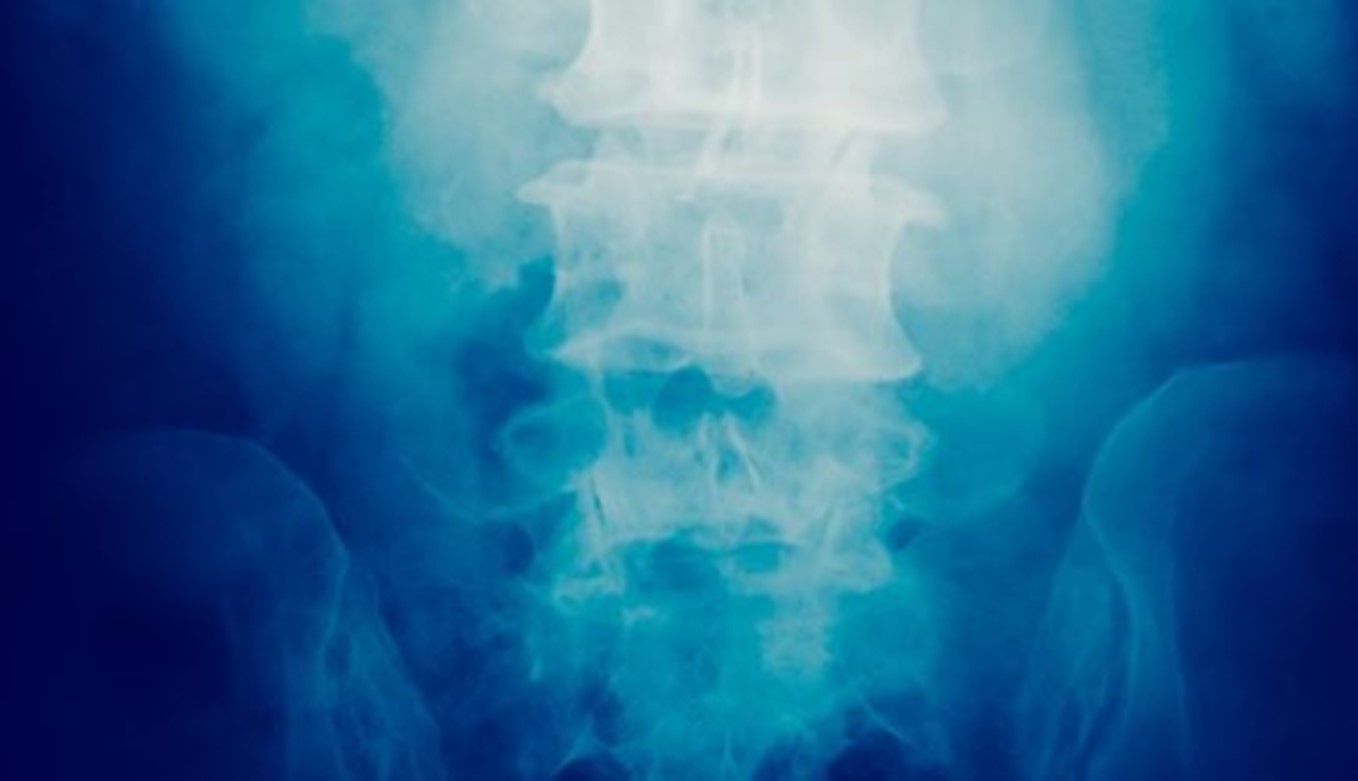

Spinal Injuries